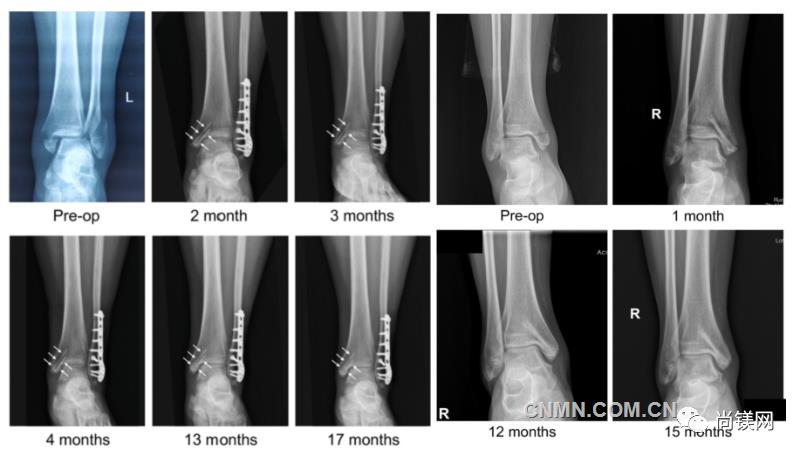

近日,国际骨科临床转化期刊《Journal of Orthopaedic Translation》在线发表了由上海交大戴尅戎院士、郝永强教授团队和丁文江院士、袁广银教授团队合作发表的可降解镁合金骨钉1-2年的临床试验观察结果,所有患者术后内踝骨折愈合,功能恢复。研究证实了可降解镁合金螺钉治疗内踝骨折的临床疗效及其生物安全性,为全降解镁合金植入物等高端医疗器械进一步的临床推广应用奠定了坚实基础,相关成果以“Effectiveness and safety of biodegradable Mg-Nd-Zn-Zr alloy screws for the treatment of medial malleolar fractures”为题在线发表于Journal of Orthopaedic Translation,27 (2021) 96–100。这是国内首个可降解医用镁合金临床试验的公开报道,也是国际首款含有功能涂层的可降解镁合金骨钉的临床试验结果的公开报道,具有里程碑意义。